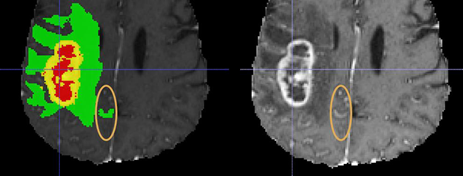

Building upon observations during all previous BraTS instances, we note some common errors in the automated segmentations. The most typical such errors observed are:

1. 1.

The choroid plexus and areas of T1 bright blood products (when they can be discriminated by comparing with the pre contrast T1 images), have erroneously been labelled as ED (Fig. 2(a)).

2. 2.

Vessels within the peritumoral T2 FLAIR edematous area, have been marked as ET (Fig. 2(b)).

3. 3.

Vessels within the peritumoral T2 FLAIR edematous area, have been marked as ED (Fig. 2(c)).

4. 4.

Periventricular white matter hyperintensities being confused and segmented as tumor/peritumoral regions (Fig. 2(d)).

Refer to caption

(a) Choroid plexus erroneously marked as ED.

(b) Vessels in ED marked at ET.

(c) Vessels in ED

(d) Periventricular white matter hyperintensities. Figure taken from [41].

Figure 2: Common errors expected from the automatic segmentations.